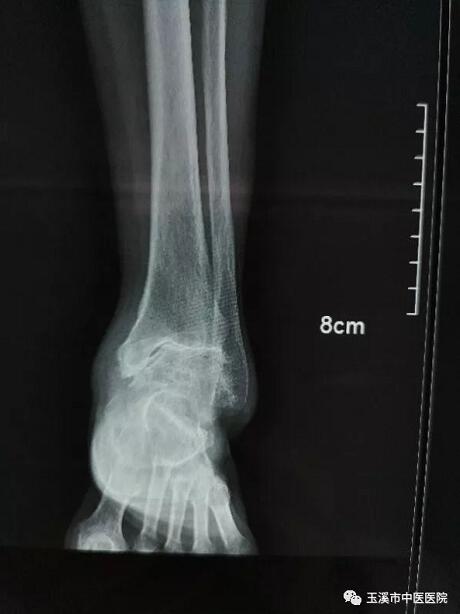

在醫(yī)務(wù)人員緊張的情況下,骨傷Ⅰ科克服種種困難,先后派出3名一線醫(yī)務(wù)人員赴千里之外的德欽縣人民醫(yī)院進(jìn)行對口援助。朱金富醫(yī)生是今年8月份去到藏區(qū)的,一到那里便積極投入工作。一位五十六歲藏族阿媽來到醫(yī)院看病時(shí),左踝關(guān)節(jié)疼痛、畸形三十余年了。 朱醫(yī)生將她收治入院,在相關(guān)檢查后,為她做了左踝關(guān)節(jié)融合術(shù)。術(shù)后藏族阿媽左踝關(guān)節(jié)功能明顯改善,生活及勞動(dòng)能力有所恢復(fù),一家人皆大歡喜。

術(shù)前X光片(左踝關(guān)節(jié)正位)